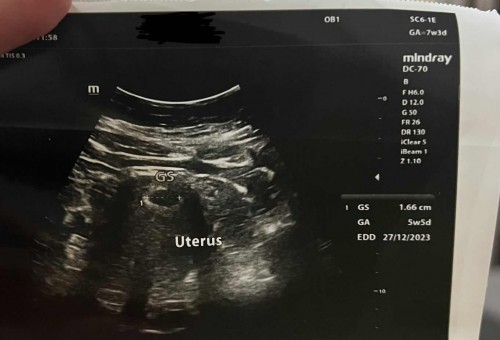

LMP : 10.3.2023 GA : 7w 3d Tapi bila scan, 5w 2d je. Janin pun tak nampak. Sy risau sangat 😖😞 Ada tak yg macam saya? Normal ke tak ye?